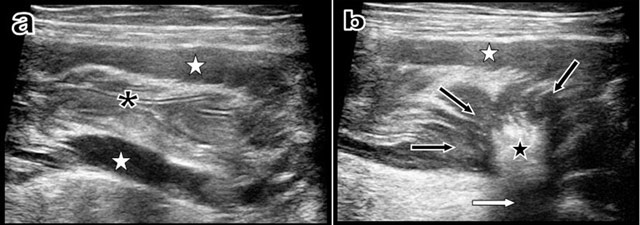

Additional ultrasound (Figure 3) study showed a perfectly empty descending colon with a normal mucosal relief, but with a thickening of the muscle layer. At the junction of the sigmoid and descending colon, ultrasound demonstrated a centripetal retractile convergence of the muscle layers to an intraparietal very hyperechoic and very attenuating scar.

Figure 3

Longitudinal ultrasound view (a) of the descending colon just proximally to the stenosis shows that the colonic lumen is absolutely empty with normal mucosal folds (black asterisk). Nevertheless, hypertrophy of the muscular layers is evident (white stars). Another longitudinal ultrasound view (b) obtained just at the level of the retractile “scar-like” process shows the retractile centripedic convergence of the muscular layers (black arrows) towards a sharply well-delimitated hyperechoic (black star) and hyper-attenuating intraparietal scar (white arrow).

Nevertheless, in the reported case, the curvilinear band-like aspect of the retractile stenosing process was very evocative of a fibrous band on CT views. Moreover, ultrasound was also very sensitive, excluding the presence of macroscopic tumoral mass and clearly showing a typical hyperechoic and hyperattenuating scar.